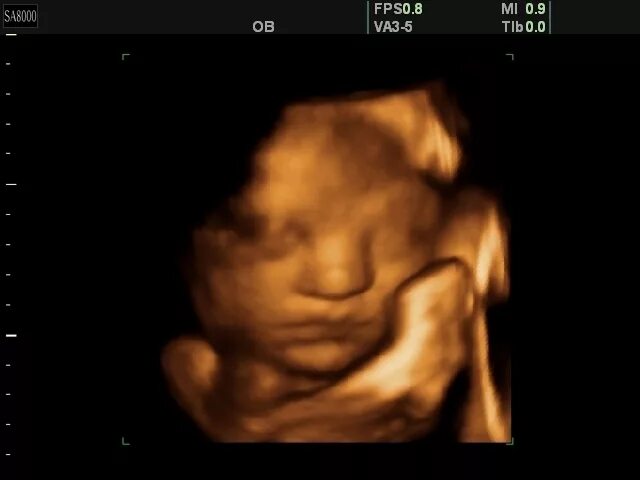

Как выглядит ребенок в 34 недели